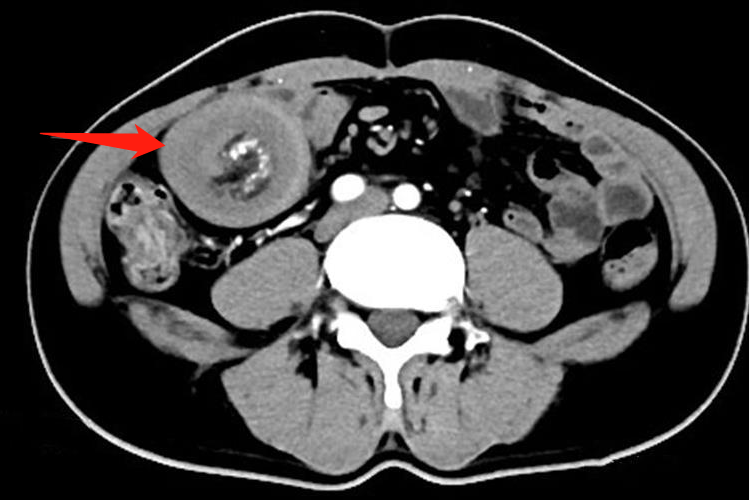

对于出现肠套叠的患者,CT检查常表现为腹腔内软组织肿块影,肿块呈高低密度相间的分层状或环状,分别代表套入部肠腔、肠壁、肠系膜脂肪及鞘部肠腔和肠壁,靶心为套入部的肠腔,其周高密度环为肠壁。增强扫描肠壁有明显强化。口服造影剂进入套入部,则靶心密度很高,CT表现以套入的肠系膜脂肪形成新月形或半环形的脂肪密度区最具有诊断特征。